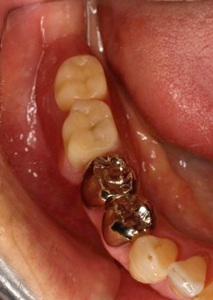

メタルボンド症例

治療前治療前主訴-前歯部の咀嚼不全と審美障害。ブリッジ(固定橋義歯)のために歯を削ったところ 作業模型上のブリッジ作業模型上のブリッジ作業模型上のブリッジ 口腔内装着口腔内装着口腔内装着